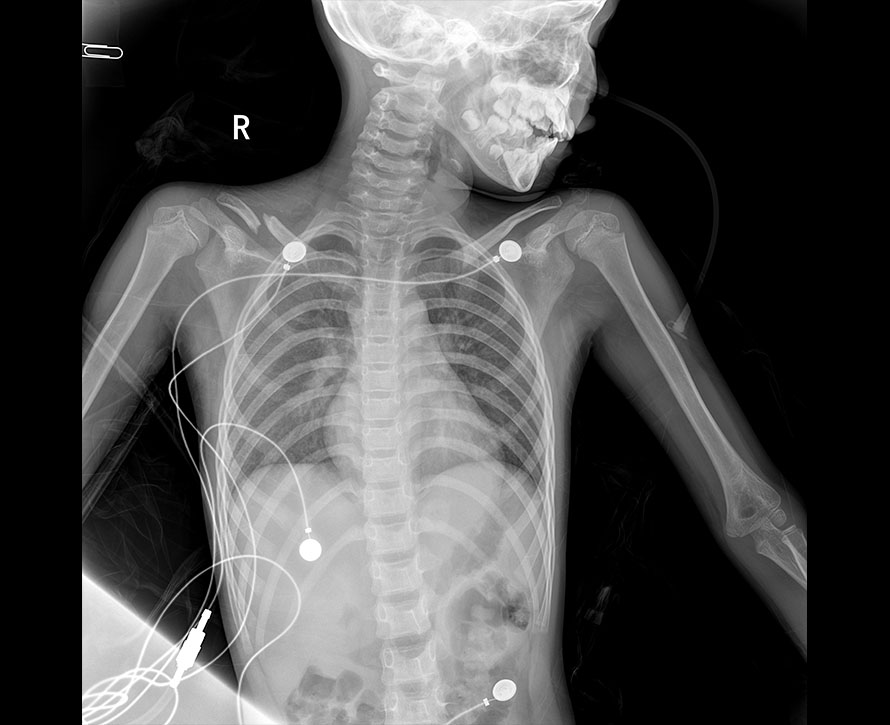

临床图像